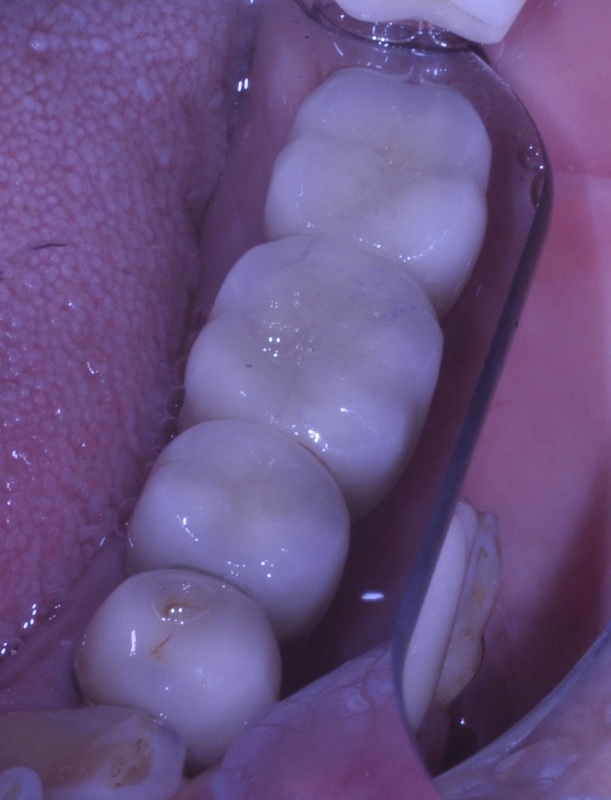

IMMEDIATE LOWER MOLAR REPLACEMENT

This type of cases Dr. Andrews encounters on a regular basis.

A 30 year old was concerned with the discomfort next to his impacted wisdom tooth and pain associated with cold and hot temperatures around the decayed back teeth.

After thorough dental examination Dr. Andrews recommended to extract the wisdom tooth (#17) and the second molar (#18) due to severe decay and poor prognosis for both teeth and to replace the second molar (#18) with a dental implant.

During only one 45-minute surgery both teeth were removed, a minor bone graft was placed and a wide-diameter (7 mm) dental implant was immediately inserted to replace the second molar. Four months later , #18 implant was restored with an all-ceramic crown.

Revolutionary digital scanning technology and CAD/CAM fabrication process had been used by Dr. Andrews to create an ideal emergence profile, ideal bite and natural anatomy for the crown.

Cavities on other teeth were treated with mercury-free, bio-mimetic white composite fillings.